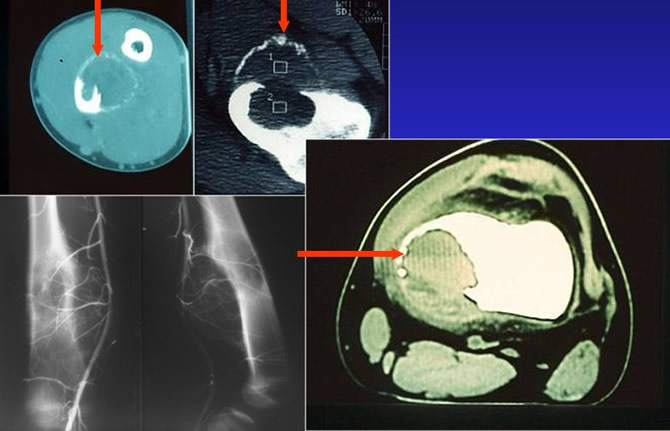

Aspect tomodensitométrique typique

Persistance d'une corticale continue, parfois en pointillée

Respect du cartilage articulaire

Pas d'envahissement des parties molles

Tumeur agressive : rupture corticale et envahissement des parties molles

La tumeur à cellules géantes bénigne peut envahir les parties molles

Bilan d'extension locale : Le scanner

Le scanner montre parfois des niveaux liquides précise les limites en coquille d'oeuf.

La scintigraphie est modérément positive.

L'artériographie ou l'angio IRM montre les pédicules artériels et permet de discuter une embolisation.